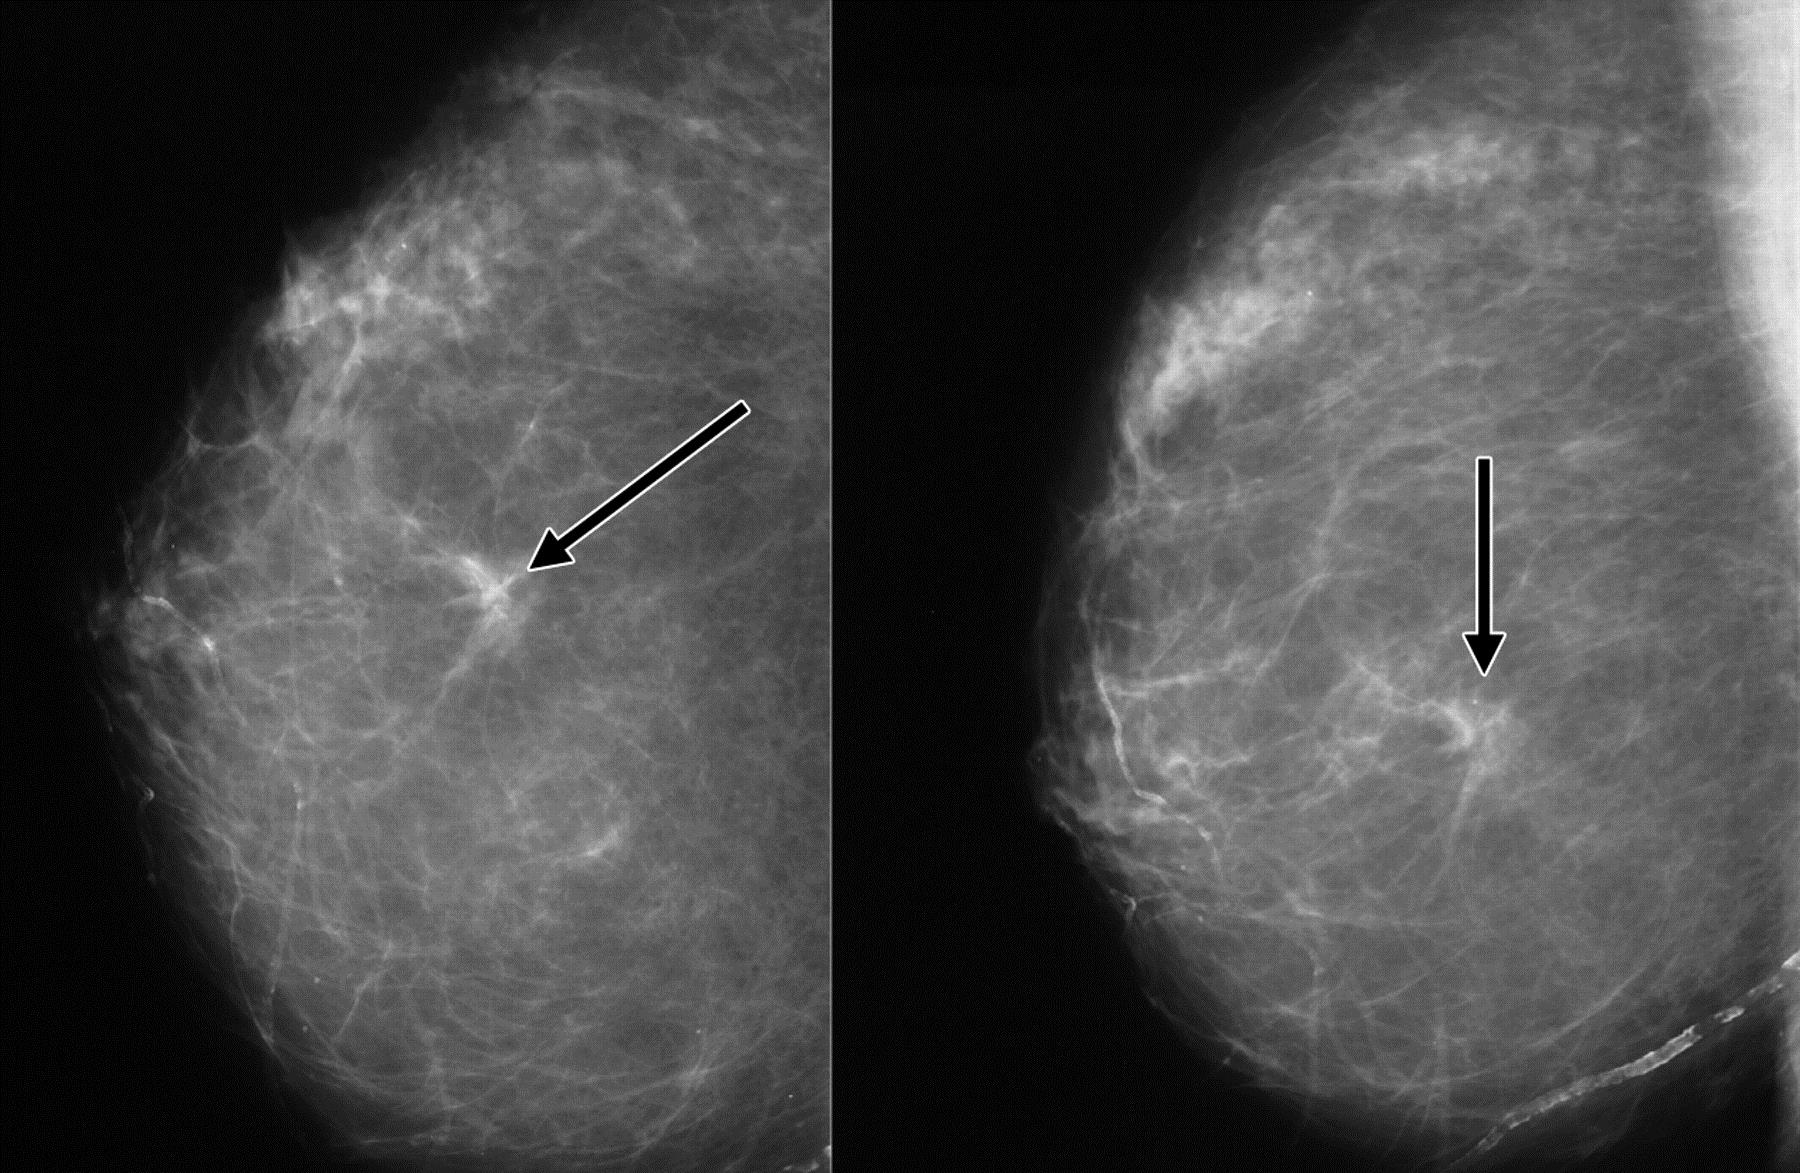

Феномен гипердиагностики в маммографии: примеры и иллюстрации

Раздел: Образы вокруг